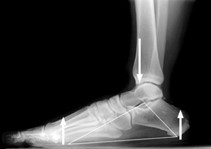

Kalkaneus, metatarzalne kosti i metatarzofalangealni zglobovi čine trokutastu strukturu nalik na luk. Plantarna fascija ide od kalkaneusa do glava metatarzalnih kostiju i falangi, te nalikuje na strunu na luku. Pri stajanju vertikalne sile od tijela idu dolje preko tibije i nastoje izravnati medijalni uzdužni luk. Sile reakcije tla jednake su, ali suprotne sili kojom stopalo djeluje na tlo, te sile djeluju prema gore na kalkaneus i glave metatarzalnih kostiju. Na taj način reaktivne sile slabe učinak izravnavanja stopala (33). Plantarna fascija zahvaljujući svojoj anatomiji i građi te pojačanoj napetosti sprječava kolaps stopala (9).

Radiografske snimke bočni i aksijalni prikaz, mogu biti od pomoći u prepoznavanju stres fraktura kalkaneusa ili petnog trna.